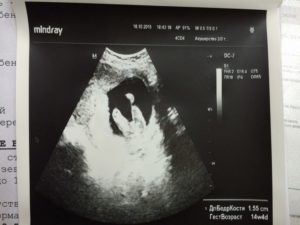

На 15 неделе беременности пол будущего малыша можно определить с помощью аппарата ультразвукового исследования. Однако следует отметить, что на таком раннем сроке весьма вероятна ошибка в результатах УЗИ.

Невзирая на то, что на 15 неделе половые органы крохи уже начинают формироваться, рассмотреть их можно только на самом современном оборудовании.

В зависимости от срока беременности и положения плода, врач может точно сказать, вынашиваете ли вы мальчика или девочку.

Чаще всего метод определения пола ребенка по УЗИ наиболее точный на сроке от 18 до 26 недель беременности. Хотя новые технологии УЗИ могут определять пол ребенка и на более раннем сроке 12-13 недель.

До 18 недель внутриутробного развития, мужские и женские половые органы больше похожи и потому вероятность ошибки высока. Более поздние сроки также усложняют эту задачу из-за более тесного положения плода.

Кольца пуповины или ручки ребенка иногда воспринимаются как пенис мальчика, и потому могут возникать ошибки в определении пола крохи, которые при следующем УЗИ исправляются.